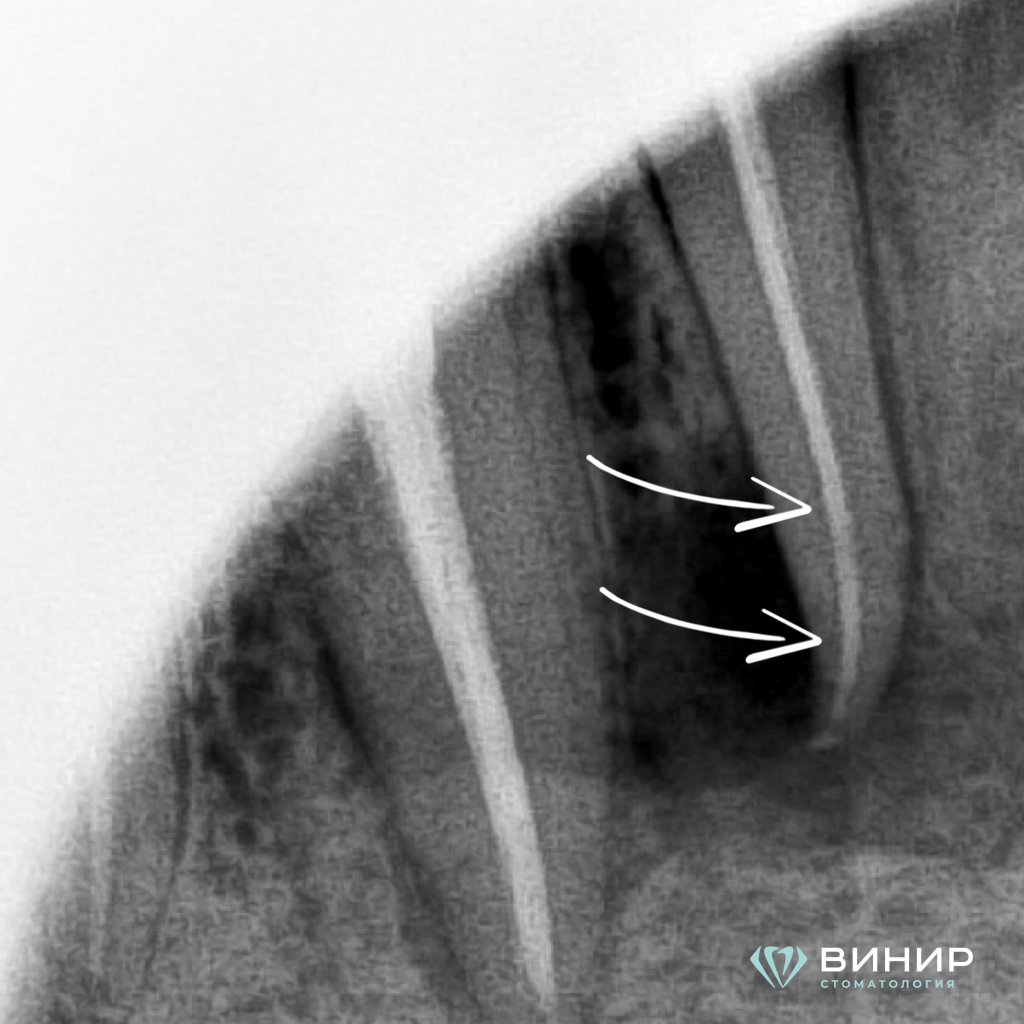

Пациенту проведено эндодонтическое лечение корневого канала зуба 4.2 с использованием операционного микроскопа, пломбирование и компьютерные рентгенологические снимки.

2. Инструментация

2 пункт.PNG